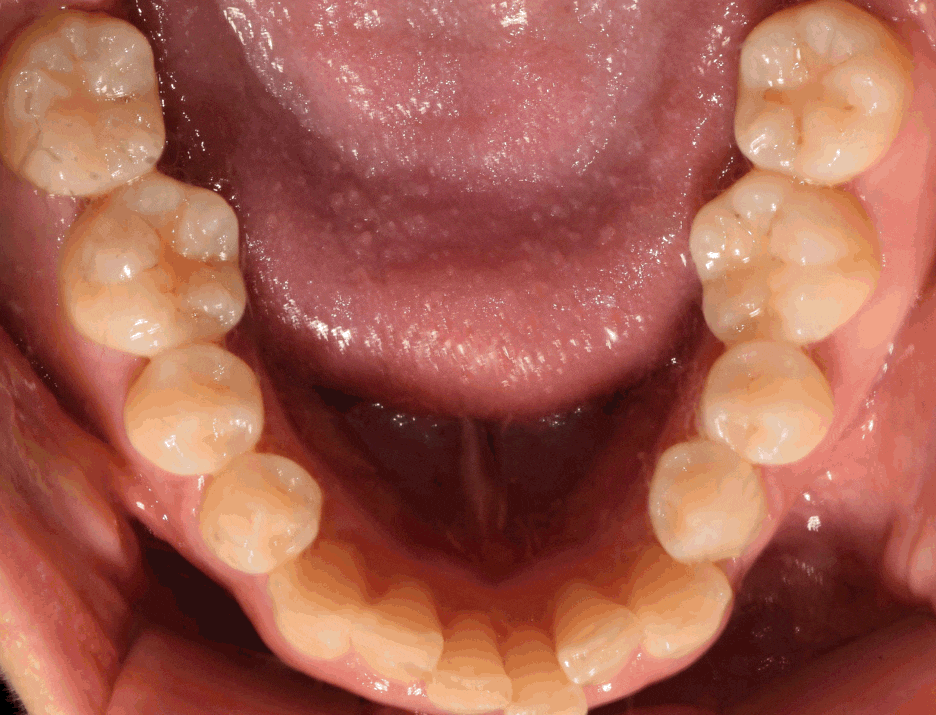

이제 최종 결과를 보여드리겠습니다.

이제, 흡잡을 곳이 없군요.

교정치료 및 발치와보존술, 임플란트 시술의

복합 결과를 보고 있으며 3년이라는 긴 기간이

소요되어서 원래의 구강 내 상태를 되찾아드렸네요.